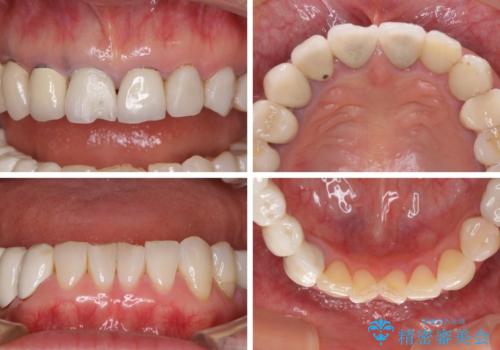

- 以前治療した歯が欠けたり、痛みを感じたりしているとのことで来院された患者様です。

アメリカ国内を転々としながら治療を行ったため治療跡がモザイク様で、クラウンが壊れていたり、抜歯が必要であったりしていました。

上下左右すべての奥歯に処置が必要であり、同時に行うと食事が取りにくくなってしまったり、手前の歯に負担がかかって初診時よりも状況が悪化したりする可能性があるため、片方ずつ処置を進めて行くこととしました。

下顎右側は骨造成を併用してインプラント治療を行い、その他の奥歯もインプラントや歯周外科処置を併用して補綴治療を進め、最後に前歯部の欠けてしまったセラミッククラウンを作り替えることとしました。

海外を拠点に仕事をされているため、日本国内への入国規制の時期が重なってしまい、予定していたよりも1年ほど長い治療期間がかかってしまいました。